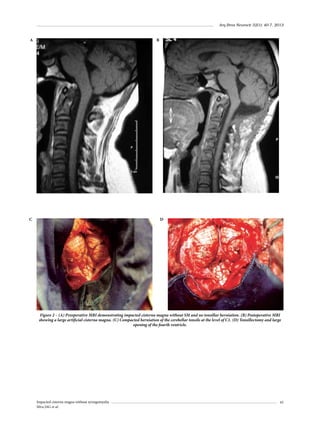

2009;49(12):587-9.

Paiva WS, De Andrade AF, Amorim RL, Figueiredo EG,

Teixeira MJ. Traumatic pseudoaneurysm of the middle

meningeal artery causing an intracerebral hemorrhage.

Case Report Med. 2010;2010:219572.

Shah Q, Friedman J, Mamourian A. Spontaneous resolution